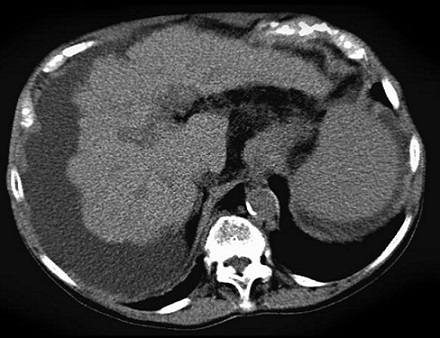

Image TDM de la

cirrhose du foie : Technique radiologique moins

sensible de dignostic cirrhose du foie au debut . Au

stade avance image radiologique TDM de la cirhose du foie

est : Parenchyme du foie est heterogene , hypertrophie

du lobe caude , index C/RL > 0.65 et signe de hypertension

portale : dilatation de la veine porte , veine

splenique , splenomegalie et image de thrombus veineuse .